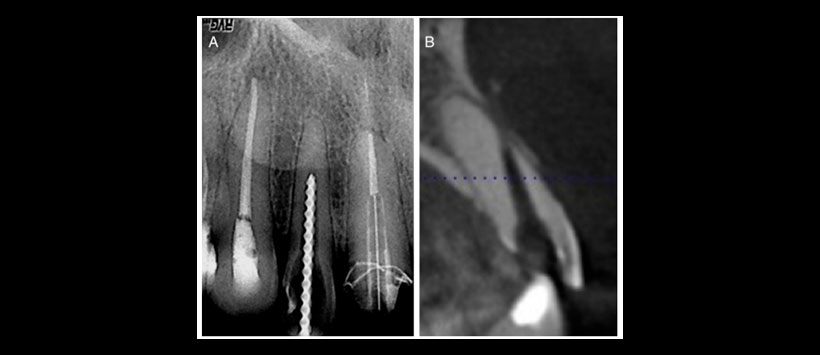

Figura 4: Radiografía periapical típica de una perforación de raíz en un incisivo superior. (A) Una imagen con lima K hasta la perforación. (B) Una exploración CBCT de la misma perforación de la raíz del diente.